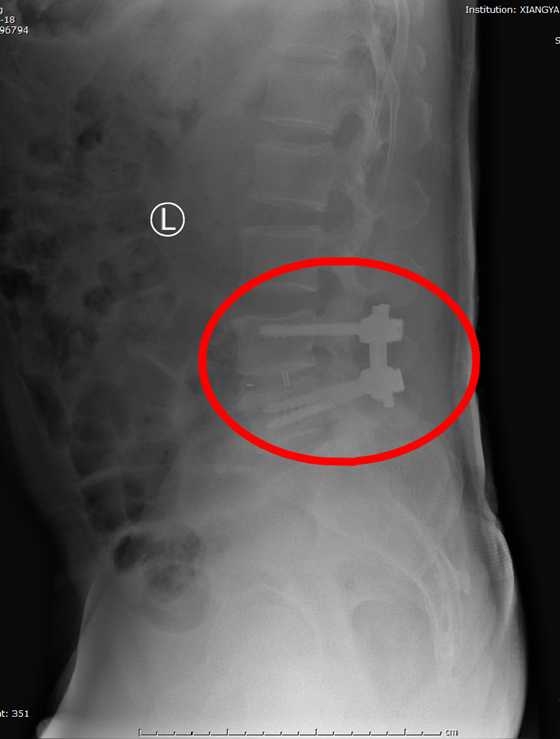

近日,骨科脊柱耗材集中带量采购经过一年多的准备工作终于如期落地,本次脊柱耗材集采平均降价84%。湘雅常德医院骨科积极响应湖南省医疗保障局发布的《关于做好国家组织骨科脊...